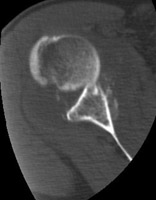

- Click on the image for a larger versionCAxial CT. This image shows a Bankart fracture.

- Click on the image for a larger versionDAxial CT. This image demonstrates the anteriorly dislocated humeral head, the source of the Bankart fracture